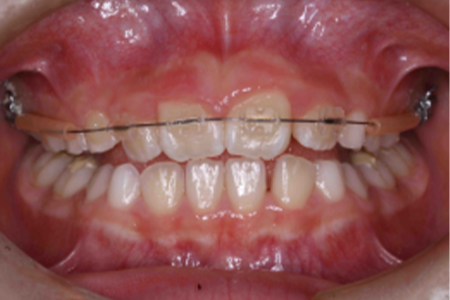

| 治療の経緯 | お母さまが子供の前歯の歯並びが気になるとのことで来院。 |

| 治療方法 | 右上2番が内側に入り込んでいる、部分的な反対咬合でしたので、 永久歯にだけ矯正装置をつけ、ワイヤーの力で、歯並びを改善しました。 |

| 治療期間 | 8ヵ月 |

|---|---|

| 費用 | インプラント 37万円×2本 骨造成 15万円 インプラント補綴 メタルボンド 15万円 |